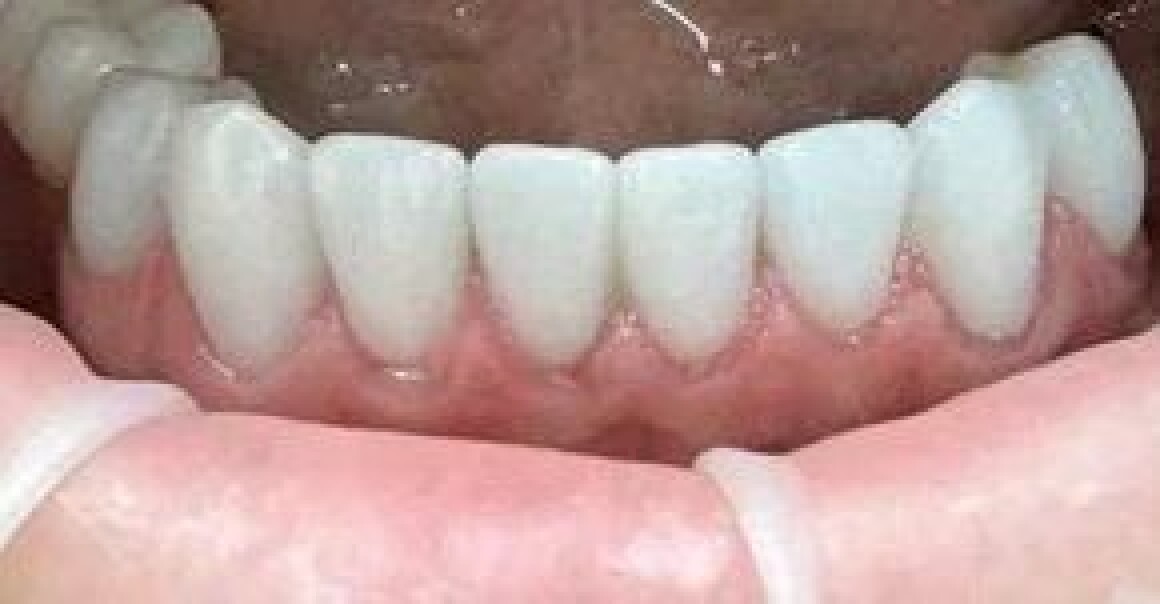

• Изготовление временных конструкций на имплантантах

• Установка временных коронок на имплантантах